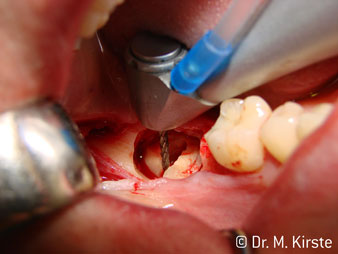

La concezione professionale del sistema di cuscinetti nel cuore della testina del contrangolo assicura un funzionamento silenzioso delle frese; durante l'estrazione di denti e radici (Fig. 4 - 9) si ottiene un taglio estremamente preciso e stabile.

Fig. 4